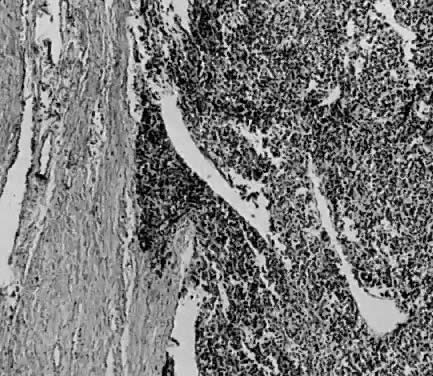

Microscopic.

Endometrial stromal sarcomas are composed of monotonous sheets of cells with basophilic nuclei and scant cytoplasm. These cells are usually round with dark-staining nuclei and resemble cells of the endometrial stroma as opposed to the long, thin, tapered cells of the uterine musculature21 (Fig. 4). Endometrial glands may or may not be present, and their absence may be the result of either an atrophic endometrium or replacement by the stromal sarcoma. The endometrial stromal sarcoma may invade the myometrial smooth muscle to various degrees (Fig. 5).

Fig. 4. Endometrial stromal sarcoma composed of nests of uniform cells with round nuclei separated by a delicate stroma. Several abnormal mitoses are present (H&E, × 350)

Fig. 5. Endometrial stromal sarcoma infiltrating between muscle bundles (H&E, × 90)